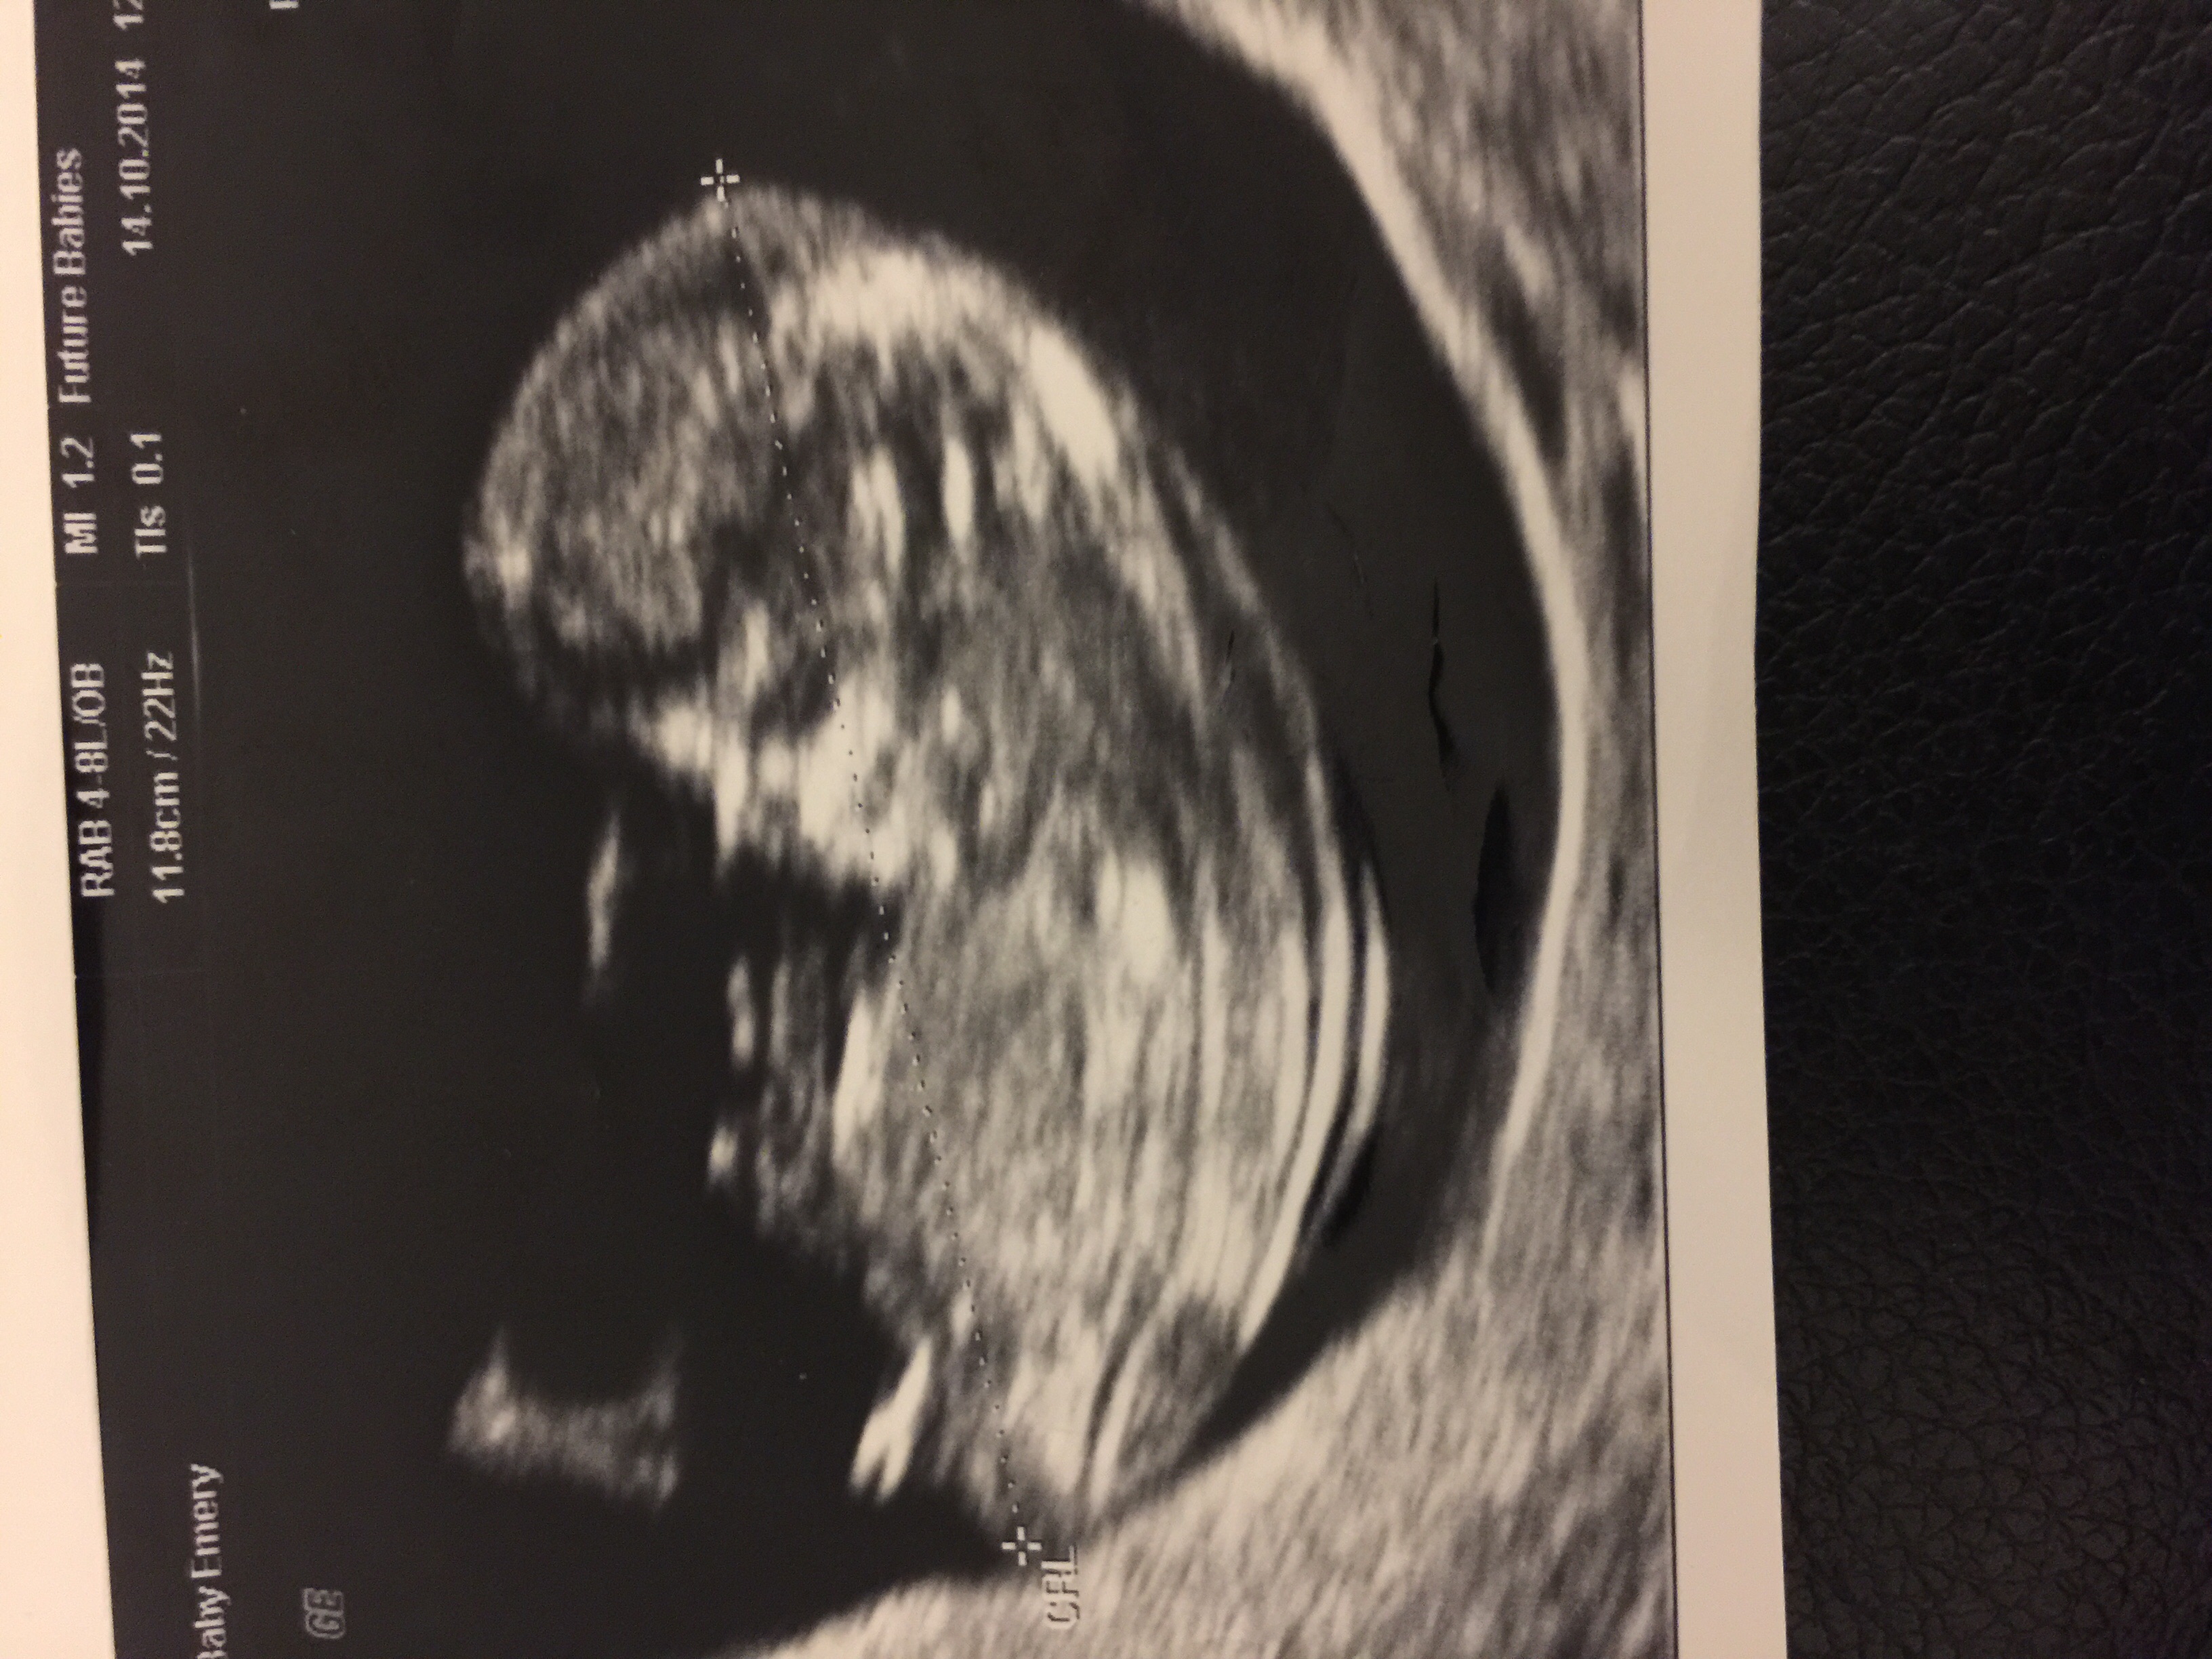

Looks boy

Thanks! I did think boy but then someone said before maybe girl because back is curved?

pretty much sticking up. boy guess

Diffently boy

Boy

Curled up baby girl.

I'd say could go either way and at 12 weeks I would lean boy x